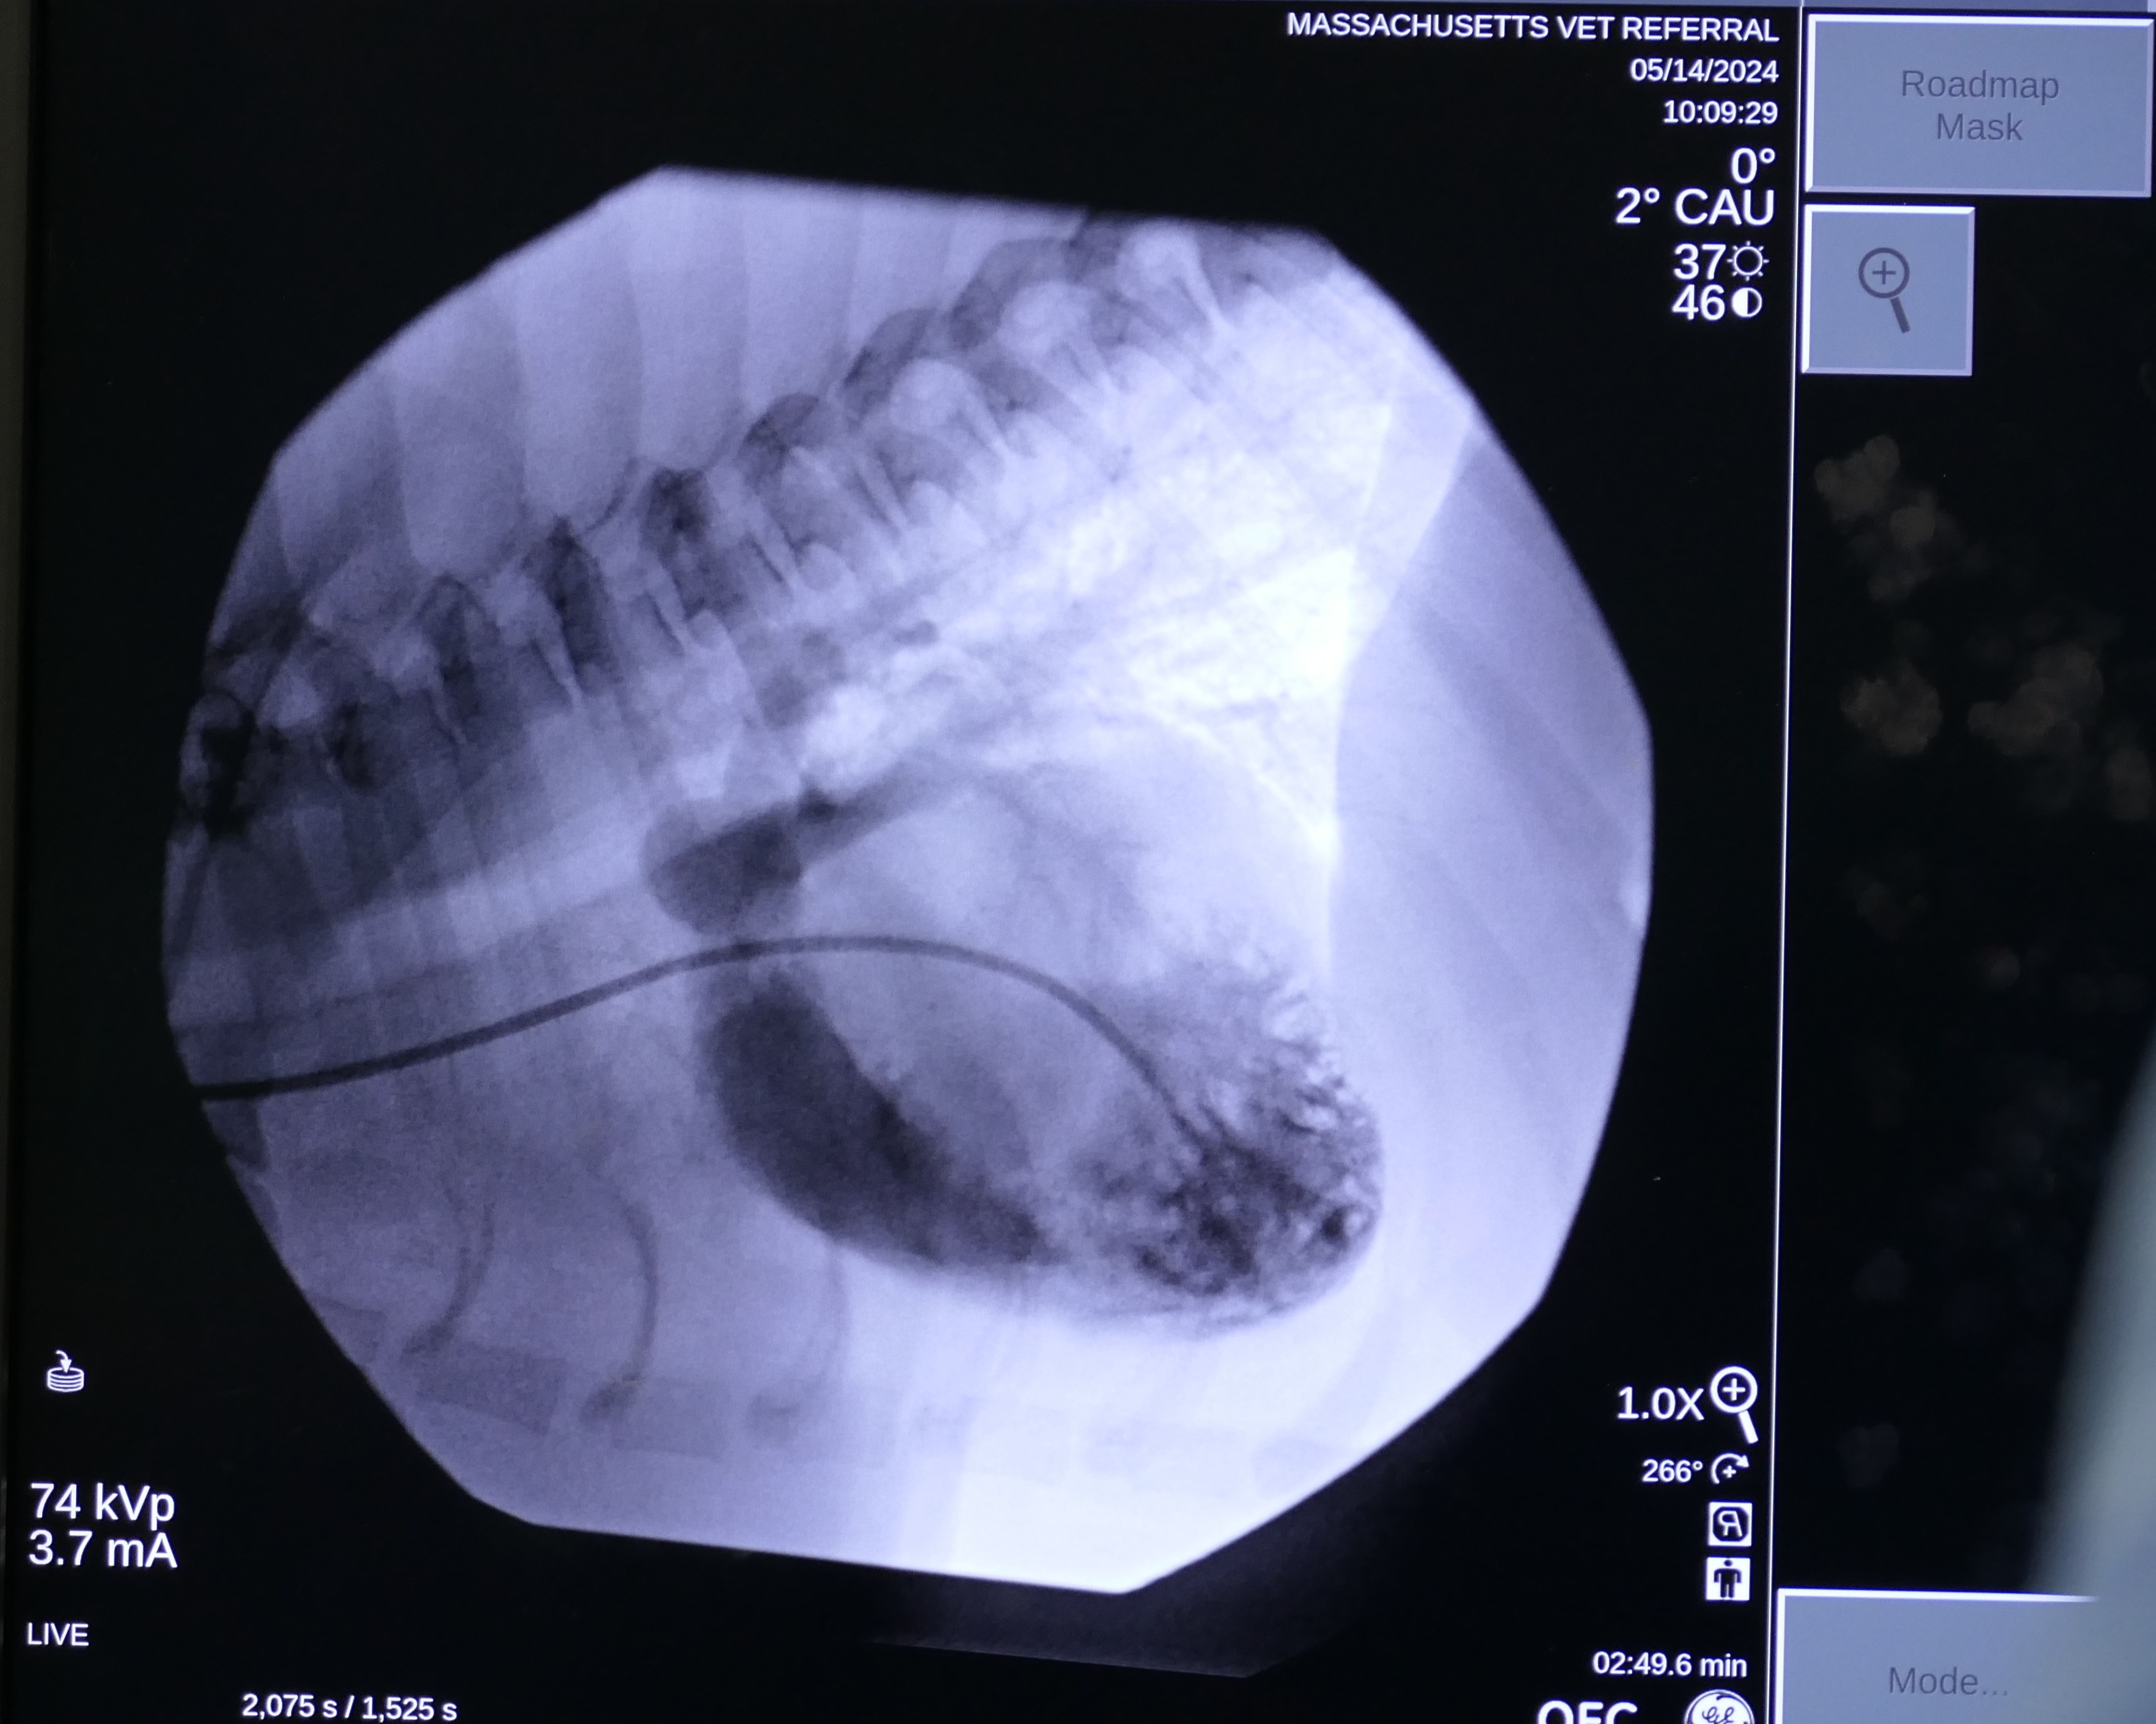

On May 7 2024, Snoop underwent a balloon valvuloplasty at MVRH. The procedure involved placing Snoop under general anesthesia and accessing the affected valve via the external right jugular vein. In order to gain access to the heart, a vascular introducer is first placed into the vein. This allows exchanging various wires and catheters without causing blood loss. Then, using fluoroscopy (Live X-rays) a catheter is advanced into the heart. This catheter has a small air balloon in its tip working as a “sail” and flowing downstream into the heart. Once the anatomy is assessed by using contrast, a Guire is placed to be used as a roadmap. Over this wire, a catheter with a large balloon in its tip is positioned across the fused valves. Once the balloon is inflated, the high pressures reached with this balloon separate the valve leaflets, decreasing the obstruction. This balloon reaches up to 18 atmospheres of pressure, and to put this in perspective, it is the equivalent of roughly stretching it with 260 pounds of force.